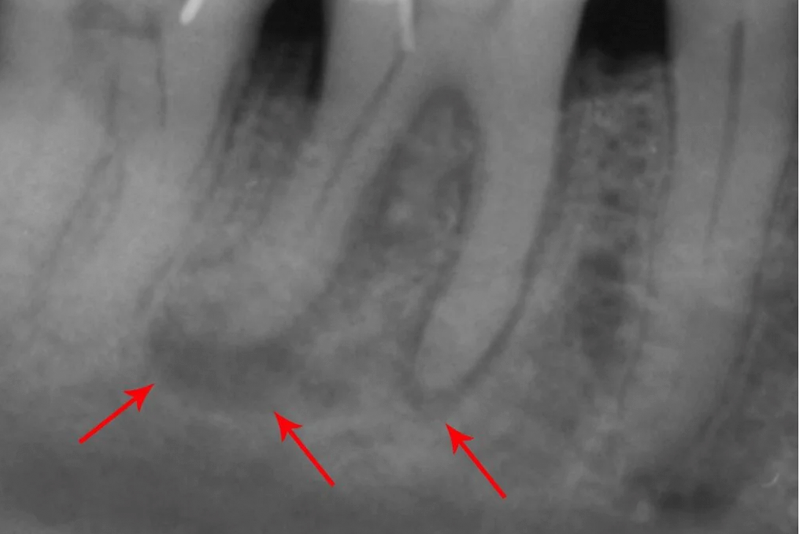

Hình ảnh áp xe quanh chóp

- Chụp X-quang: Để xác định vùng nhiễm trùng.

Chụp X-quang để xác định vùng nhiễm trùng trong áp xe răng